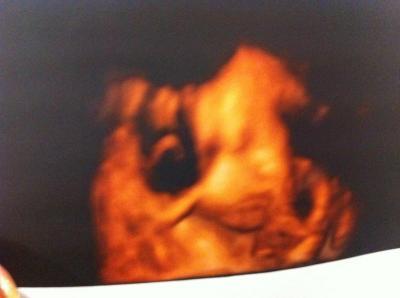

huhu ihr Lieben! Bin zurück vom Doppler. Muss jetzt wöchentlich zum Gyn und in 10 Tagen wieder zum Pränataldiagnostiker. Gebärmutterversorgung hat ordentlichen Widerstand. Muss halt unter Kontrolle bleiben. Fruchtwasser ist wenig, da ich wahrscheinlich zu wenig trinke:-( Also ab jetzt wir" gesoffen "was das Zeug hält:-))) Püppi ist fit wie ein Turnschuh und mit tatsächlichen 45 cm und 2100 kg im Normbereich. Bin super glücklich leider hatte sie die Nabelschnur im Gesicht. und somit konnte man sie nur so sehen:-) Ach ja und dann sagte Frau Doktor schauen Sie mal ... da war was das sah aus wie Algen im Wasser , so eine Art Wellenbewegung. Meine Maus hat Haare ohne Ende Wahnsinn wie man das sehen konnte. so jetzt erst mal eine Std.Bubu machen. Bin völlig k.o. Bis später lg Bianka

Bild zu Zurück vom Pränataldiagnostiker - Forum für April - Mamis